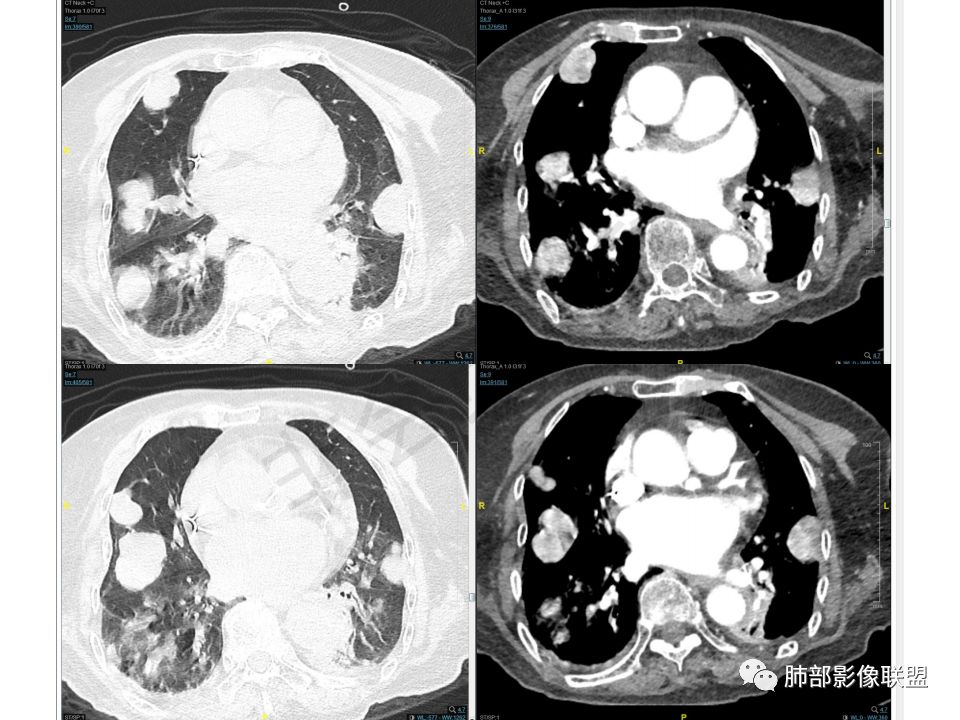

老年女性,气管腔内占位,左肺下叶阻塞性炎症伴不张,腔外病灶大于腔内,左肺门血管包埋,外缘欠光滑,似有冰山征。纵隔淋巴结,双肺多发富血供团块样转移结节。

一元论考虑肺恶性肿瘤,双肺转移瘤。

类癌支气管动脉供血,可以富血供,但易累及淋巴结和血管。

癌肉瘤可以出现明显团块样富血供转移。

晨读:老年女性,间断咯血2年,呼吸困难2月,加重3天,高血压冠心病史40余年,阵发性房颤20余年,老年痴呆10年,贫血5年,气管腔内不规则结节,强化明显,双肺多发圆形或类圆形结节,强化明显。临床症状病史加影像改变综合分析,有三种可能:1、气管原发恶性肿瘤伴肺内转移,2、气管与肺部均为富血供转移,原发待定,3、气管内良性肿瘤性结节,肺内恶性转移。个人倾向于气管类癌或非典型类癌合并肺上转移,并类癌综合征可能,其他两个可能待鉴别,建议查甲状腺,腹部CT,肿瘤标志物。